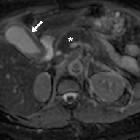

Diffusion-weighted

MRI: findings and role in acute cholecystitis. High (800) b-value diffusion-weighted images (d,e) showed visually hyperintense signal in the gallbladder wall (arrows) indicating acute inflammation, and pancreatic gland (*) gradually progressive hypersignal consistent with oedematous acute pancreatitis from tail to head.